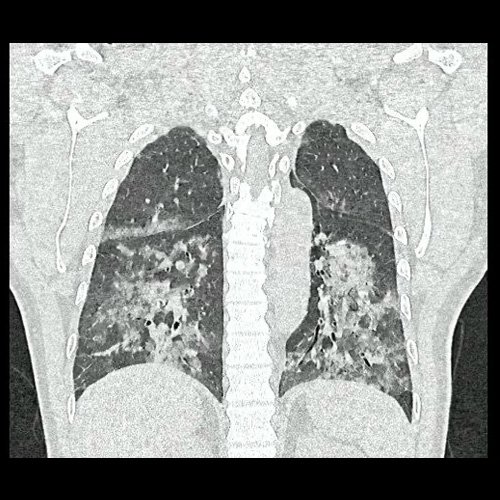

• Tomografía de tórax sin contraste endovenoso (Dia 0):Se observan múltiples áreas de consolidación parenquimatosa con broncograma aéreo y de distribución difusa por ambos pulmones, predominando en los lóbulos inferiores, asociadas a engrosamiento de los septos y rodeadas de tenue vidrio esmerilado. Se identifican estructuras ganglionares lateroaórticas, pretraqueales y subcarinales, ninguna de ellas sin alcanzar rango megálico.

Tomografia de torax sin contraste endovenosos (Ventana pulmonar- Corte coronal)